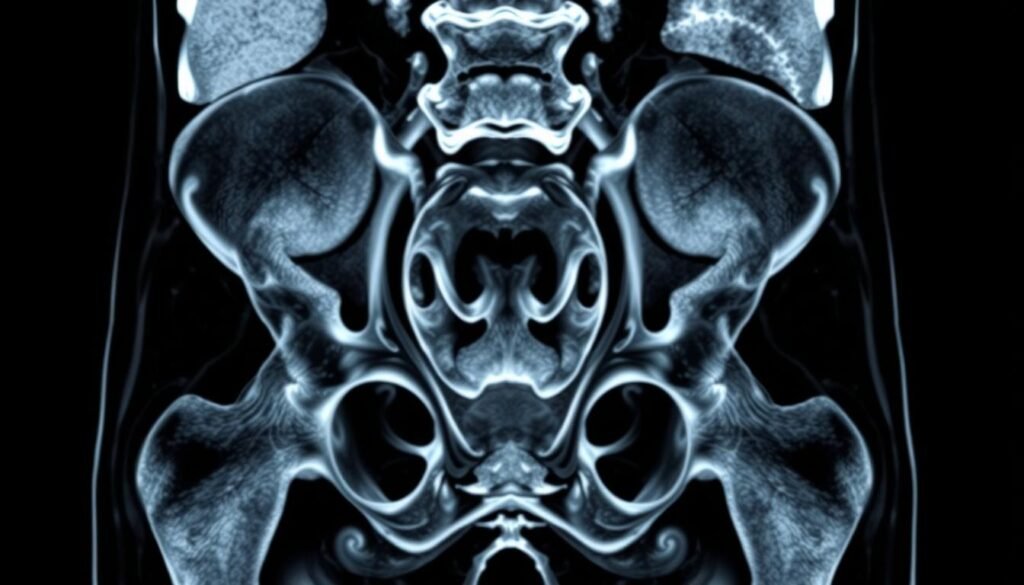

L’imagerie par résonance magnétique (IRM) est une méthode moderne et non invasive pour examiner les organes internes. Elle utilise un champ magnétique puissant et des ondes radio pour produire des images détaillées. Cet examen est particulièrement utile pour analyser la région pelvienne chez les femmes.

Comparée à d’autres techniques comme l’échographie ou le scanner, l’IRM offre une précision exceptionnelle. Elle permet de visualiser clairement l’utérus, les ovaires, la vessie et le rectum. Au Maroc, de plus en plus de centres médicaux adoptent cette technologie.

L’IRM pelvienne se distingue par sa précision inégalée dans l’étude des organes reproducteurs féminins. Cette méthode utilise un champ magnétique et des ondes radio pour générer des images en coupes fines, sans radiation ionisante.

Le principe repose sur l’interaction entre les protons d’hydrogène des tissus et le champ magnétique. Cette technologie offre une résolution spatiale de 0,5 à 1 mm, contre 2-3 mm pour une échographie classique.